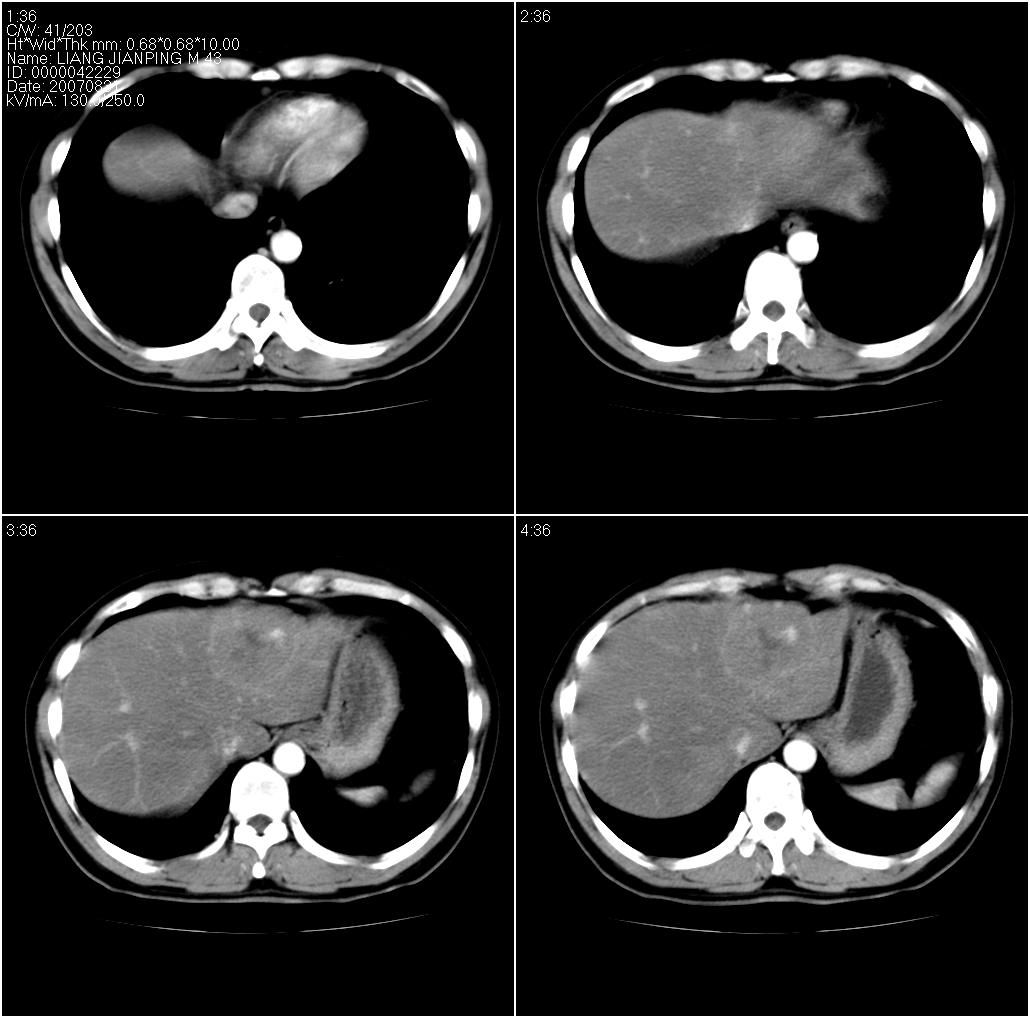

男,43岁。体检发现肝脏病变

考虑肝左叶癌并脂肪肝,肿块在脂肪肝衬托下呈高密度影,其内可见坏死灶,建议增强

肝右叶密度均匀减低,左叶增大,表面凹凸不平,内有低密度影。脾不大其密度较肝稍高。考虑1脂肪肝2肝左叶占位。建议增强。

结合增强扫描

我觉得肝左叶病变考虑fnh可能性最大。

增强后诊断很明确了,缓慢结节样强化:肝内多发血管瘤

从这个病例可以看出增强ct优势何其重要性和必要性。